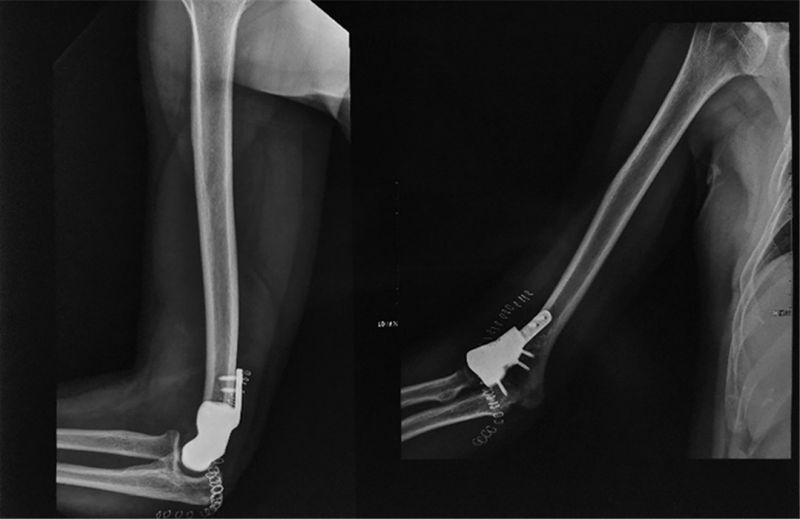

术后影像。

“该手术是我院首次采用3D 打印技术个性化定制假体,应用于骨肿瘤病人的治疗及重建,也是山东省首例。我们根据术前3D打印出来的截骨导板,将肱骨远端外侧病灶完整地精准切除,假体与切除后的骨质非常贴合;由于我们预先给假体做了多孔骨长入处理,将来假体可与正常骨质长在一起,这样假体的稳固性会非常好;术中我们重建了肘关节的功能性肌肉,所以,患者术后的屈伸及旋转功能很快得到恢复,这大大提高了患者术后的生活质量。”烟台山医院副院长常黎明介绍说,由上海交通大学医学院附属第九人民医院戴尅戎院士带领的上海交通大学医学3D打印创新研究中心成立于2016年,它是全国3D打印技术应用于临床医学的研究基地,获得国家“十三五”科技重大专项奖。而烟台山医院是烟台市骨科医学中心,其骨科是山东省临床重点专科。“我们医院在‘医工结合’的大形势下,目前已经与上海交通大学医学3D打印创新研究中心签署战略合作协议,我们也将马上成立上海交通大学医学3D打印创新研究中心烟台山医院分中心,这将进一步提升医院骨科的技术水平,切实满足更多患者的需求,让骨科疾病治疗更加个性化、精准化。”